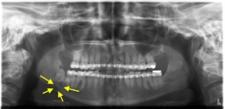

Dogo Çenesinin Gücü Ne Kadar Ton Basabiliyor?Dogo Argentino, güçlü yapısıyla dikkat çeken bir köpek ırkıdır. Bu ırk, av köpeği olarak yetiştirilmiş olup, kaslı yapısı ve güçlü çenesi ile bilinir. Dogo Argentino'nun çene gücü, hem avcılık yetenekleri hem de koruma işlevleri açısından oldukça önemlidir. Bu makalede, Dogo'nun çene gücünü detaylı bir şekilde inceleyeceğiz. Dogo Argentino'nun Çene AnatomisiDogo Argentino, güçlü bir çene yapısına sahip olmasıyla birlikte, bu güçlü yapı birkaç anatomik özellikten kaynaklanmaktadır:

Çene Gücü ve Basınç ÖlçümüBir köpeğin çene gücünü ölçmek için genellikle "bite force" (ısırma gücü) terimi kullanılır. Dogo Argentino'nun çene gücü, 450 psi (pound per square inch) civarında ölçülmüştür. Bu, Dogo'nun çenesinin yaklaşık 20-30 ton basma kapasitesine sahip olduğu anlamına gelir. Bu güç, Dogo'nun avını yakalama ve tutma yeteneğini büyük ölçüde artırır. Çene Gücünün ÖnemiDogo Argentino'nun çene gücü, birkaç açıdan önem taşımaktadır: